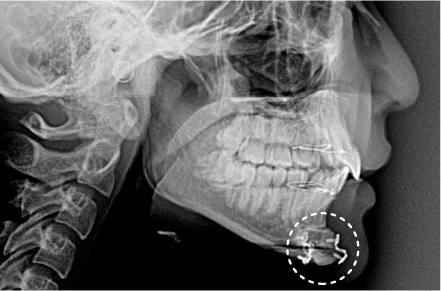

ただし、レントゲン検査でピンやプレートが映らないようにしたい・手術をしたことをできるだけバレない形にしたいといった際には、ピン除去が有効です。

- こめかみ、口腔内、目尻付近から切開を行い、頬骨弓部・体部や頬骨前頭突起付近の剥離を行います。

- 頬骨体部と頬骨弓部および眼窩外側において骨切りを行います。

- 仕上がりの輪郭をイメージしながら頬骨と頬骨前頭突起を後方に移動します。

- 移動した部位の骨の角を中心にやすりで削り、滑らかなラインになるように調整します。

- プレートで固定し骨膜と皮膚を縫合します。